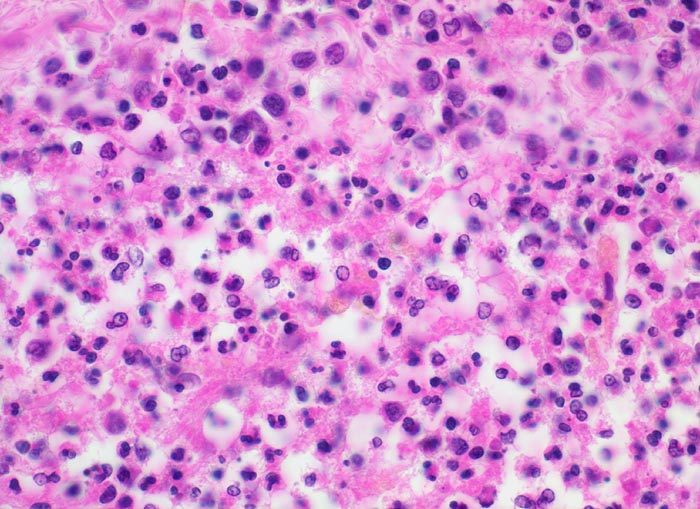

PathoPic – image database / PathoPic ID 5191 - Eitrige Leptomeningitis

Eitrige Leptomeningitis

Ausschnitt aus dem eitergefüllten Subarachnoidalraum: Wenig Fibrin, segmentkernige und stabkernige neutrophile Granulozyten, Kerntrümmer von zerfallenen neutrophilen Granulozyten.

Bronchopneumonie. Nachweis von Pneumokokken im Abstrich von der Hirnoberfläche und von der Lunge.

Kopfschmerzen seit 3 Tagen mit zunehmender Bewusstseinseintrübung, Fieber. Diabetes mellitus. Patientin stirbt kurz nach Spitaleintritt.

400